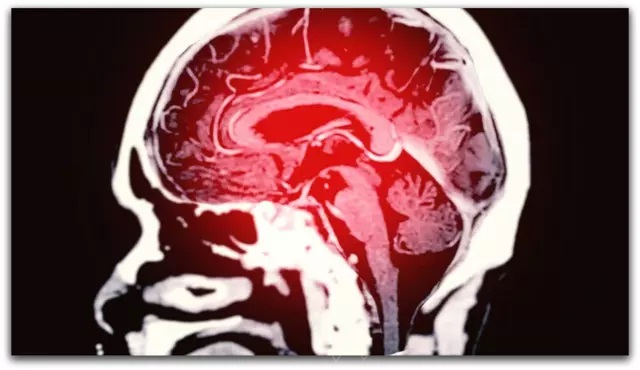

Новиот метод за предвидување на Алцхајмеровата болест до девет години однапред дава големи ветувања во борбата против болеста, благодарение на соработката помеѓу Queen Mary University во London и Monash University во Australia. Нивниот невробиолошки модел користи функционална магнетна резонанца (fMRI) за да ги анализира снимките на мозокот.

Истражувањето, кое е објавено во списанието Nature Mental Health, се фокусира на стандардната мрежа на режими (DMN), мозочен систем кој првично е погоден од Алцхајмерова болест. DMN игра клучна улога во организирањето на мислите со поврзување на различни региони на мозокот. Студијата вклучува скенирање на мозокот на 81 лице кои подоцна развиле деменција и 1.030 исти контролни лица, идентификувајќи знаци на деменција до девет години однапред. fMRI скенирањето е едноставно за изведување и трае само неколку минути.